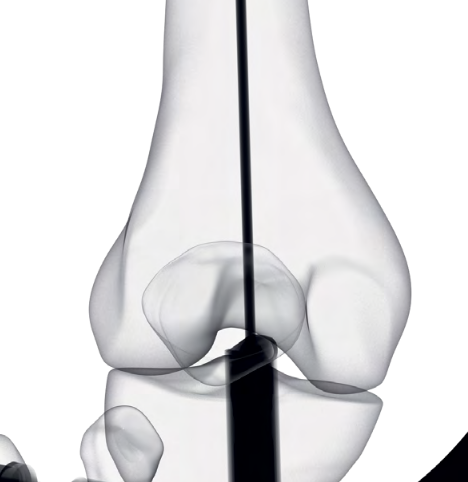

AO Classification

Types

| Type A: Supracondylar | Type B: Partial articular | Type C: Complete articular |

A1: Minimal comminution A2 / 3: Increasing comminution |

B1: Sagittal lateral B2: Sagittal medial B3: Coronal plane / Hoffa |

C1: Minimal comminution C2 / 3: Increasing comminutioin |

Lateral plate IM nail Dual plate if highly comminuted |

ORIF + lateral plate for sagittal plate Cannulated screws for coronal plane |

Dual plate Plate + nail Distal femoral replacement |